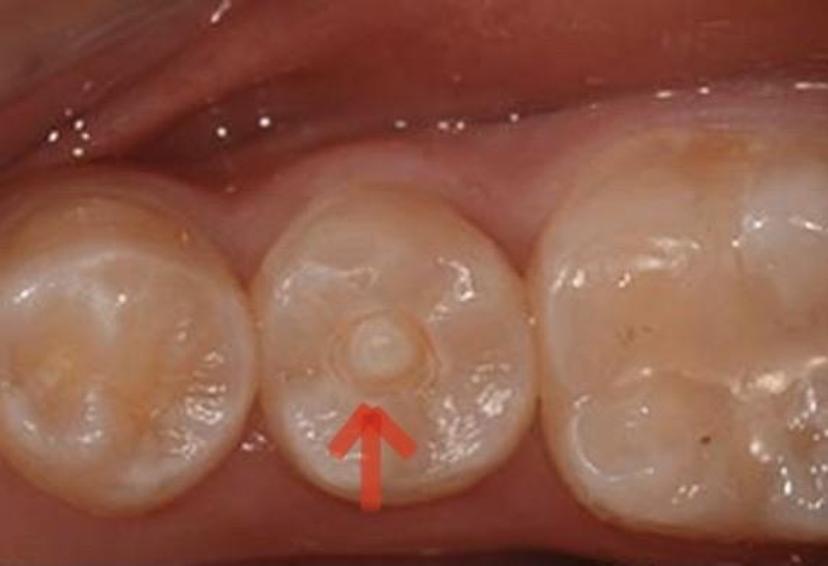

孩子恒牙萌出时,中间冒出一个白色"小尖尖"_中央尖_畸形_治疗

经过检查,医生告诉家长,孩子的牙齿发育畸形,是畸形中央尖引起的牙髓

图中突起部位即畸形中央尖,此突起极易折断,导致细菌进入牙髓.